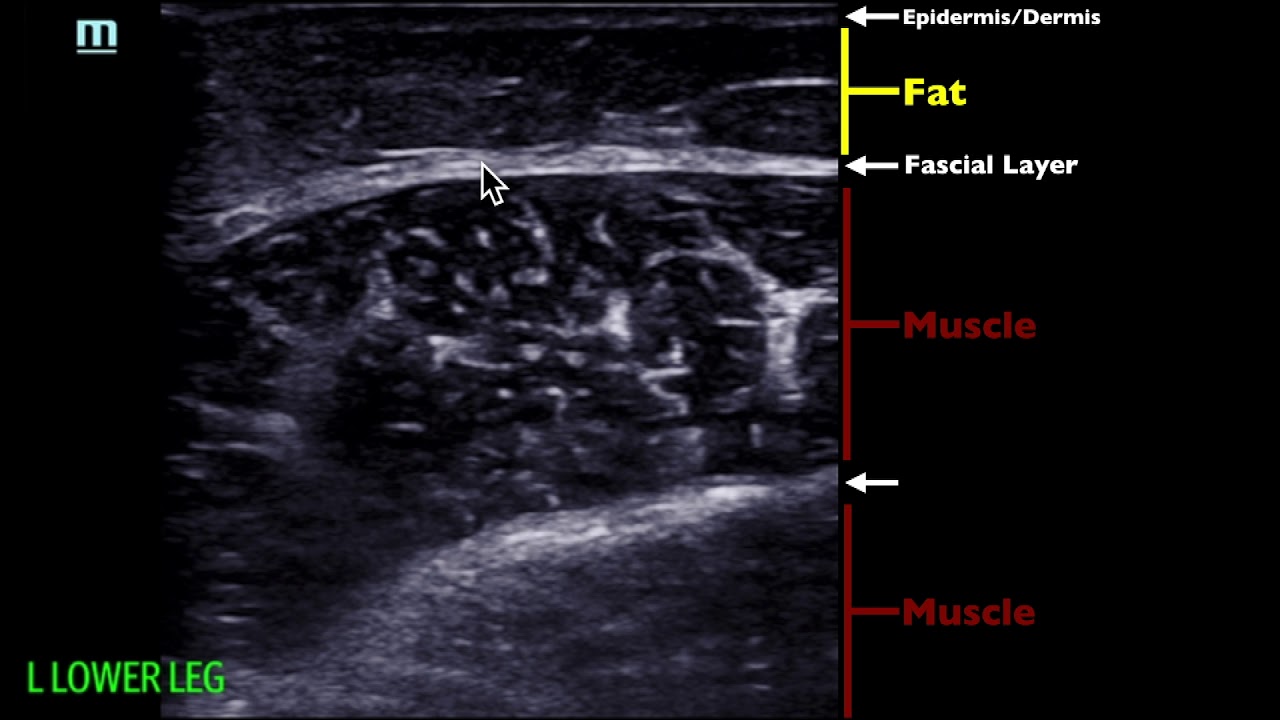

In this video, I discuss a way to help elevate your soft tissue ultrasound game by using a water bath to help visualize that abscess (or cellulitis). This technique is courtesy of Jenn Cotton!